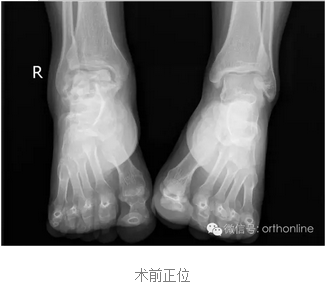

世界上首例3D打印的具有生物学功能的个性化假体治疗距骨塌陷性坏死在重庆获得成功

创伤引起的距骨塌陷性坏死一直是医学界面临的难题,治疗手段非常有限,目前只能采用以牺牲踝关节生物学功能的胫-距-跟植骨融合来缓解病人的痛苦,严重影响患者生活质量。

针对上述问题,由第三军医大学西南医院唐康来教授牵头,中国科学院重庆绿色智能技术研究院、物质结构研究所、金属研究所、化学研究所、理化技术研究所等十个单位协作攻关,分别从3D打印设备与专用材料、个体性产品开发与临床应用方面进行研究,研制了世界上首个3D打印的具有生物学功能的个性化距骨假体,于2016年7月4日在重庆第三军医大学西南医院成功应用于创伤引起的距骨塌陷性坏死病例。